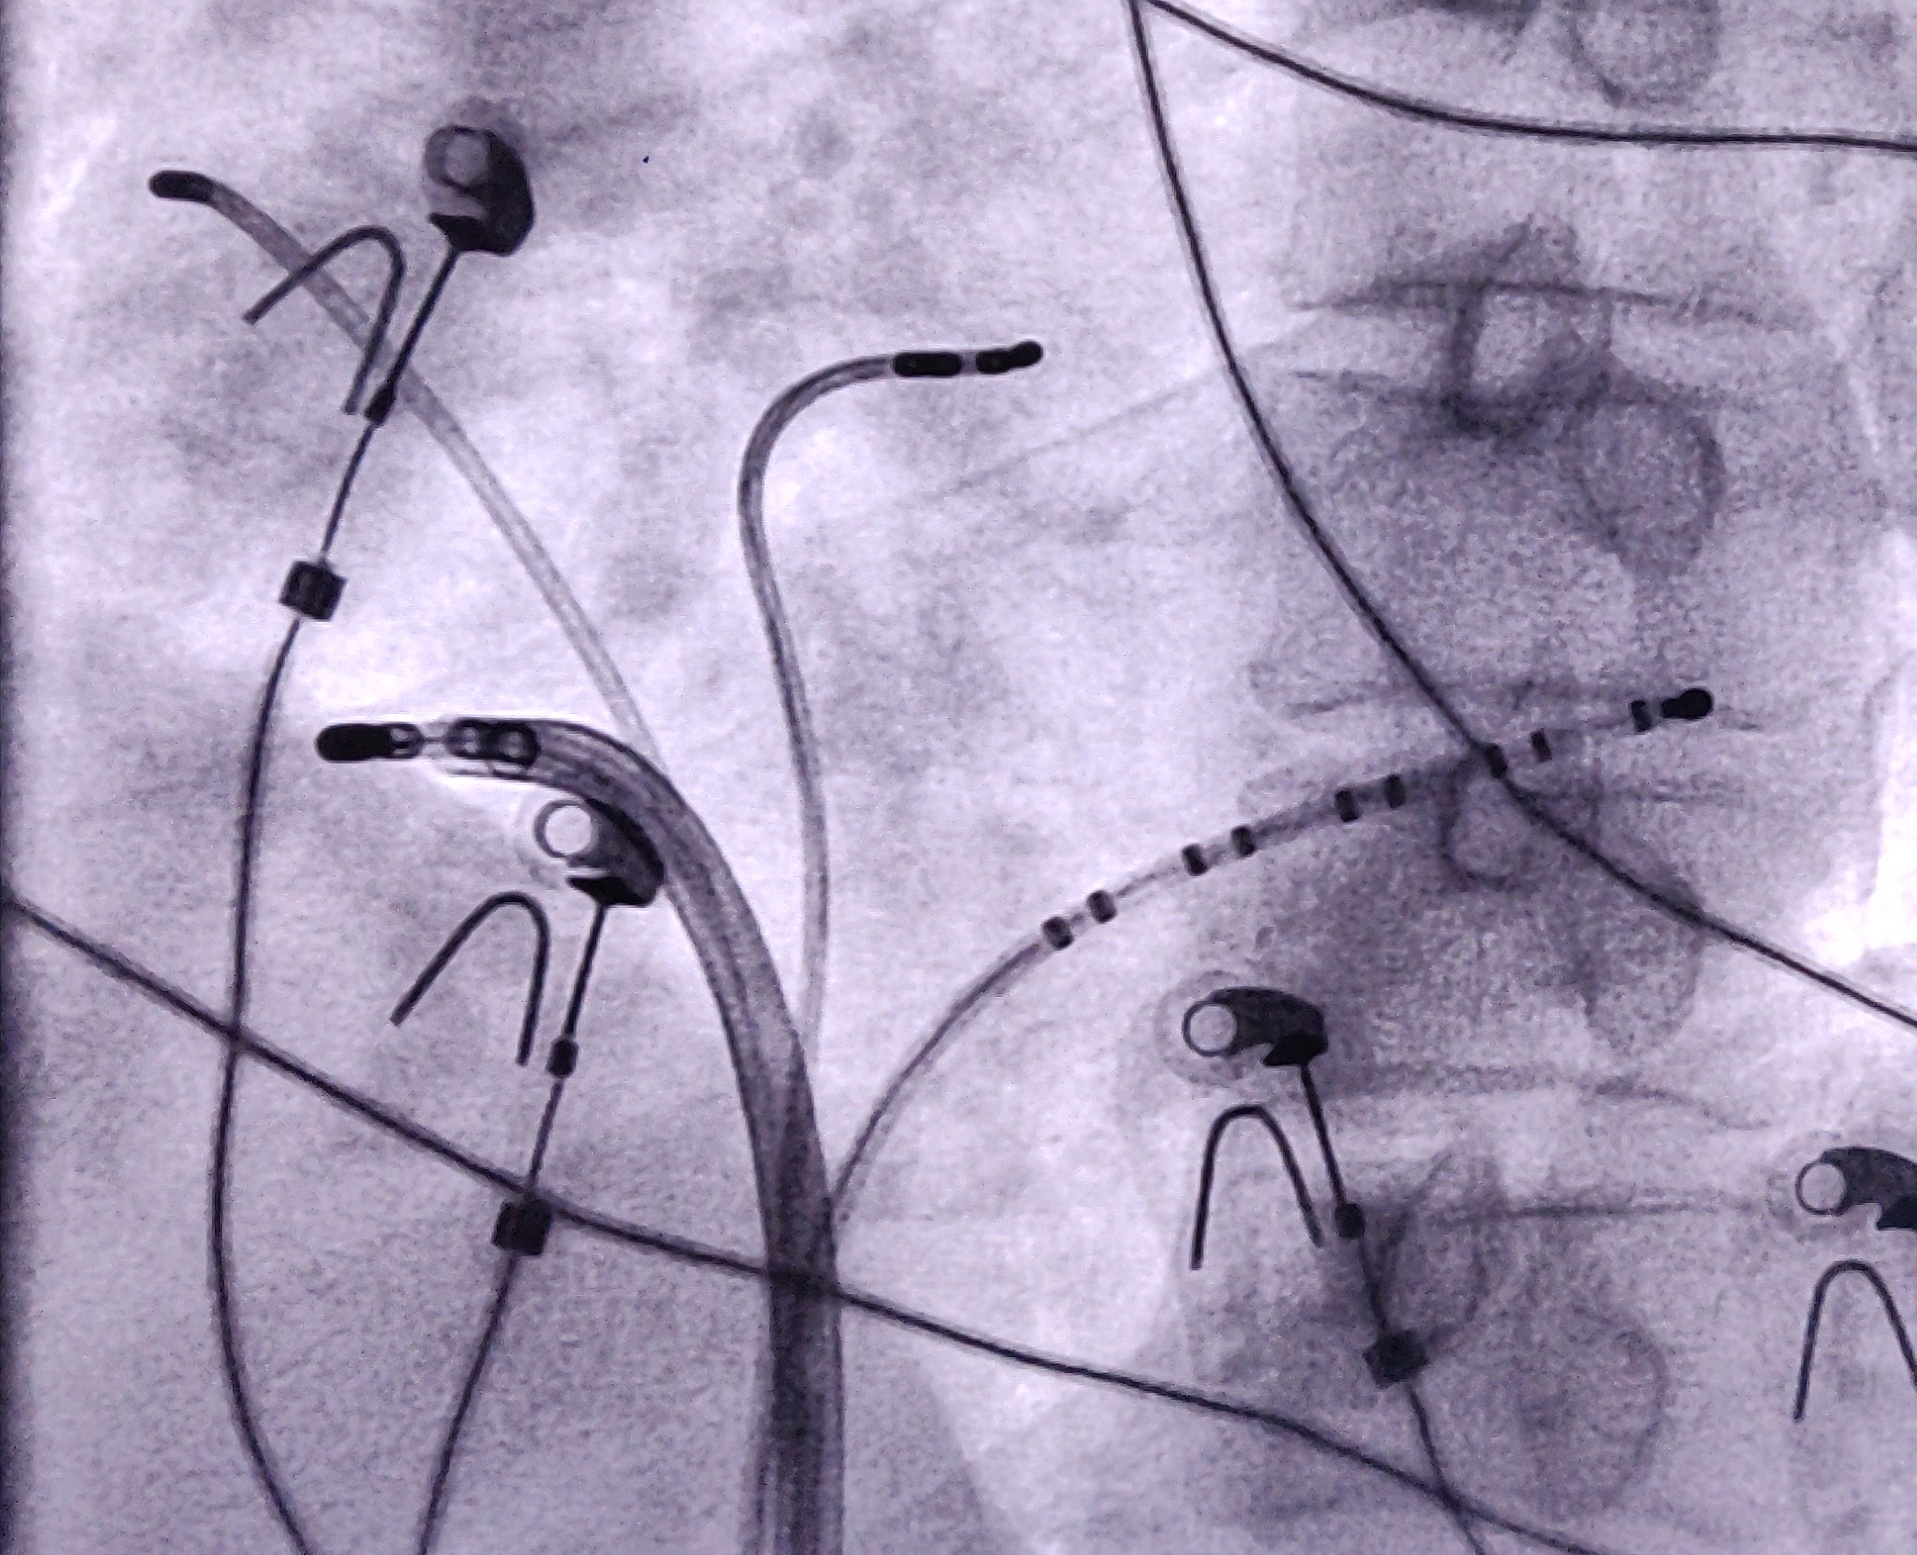

Mapping

09_ablation site.jpg